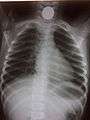

Chest radiograph showing a Venezuelan 25 cent coin lodged in the upper esophagus of a 9-year-old girl.

A coin seen on AP CXR in the esophagus

A coin seen on lateral CXR in the esophagus